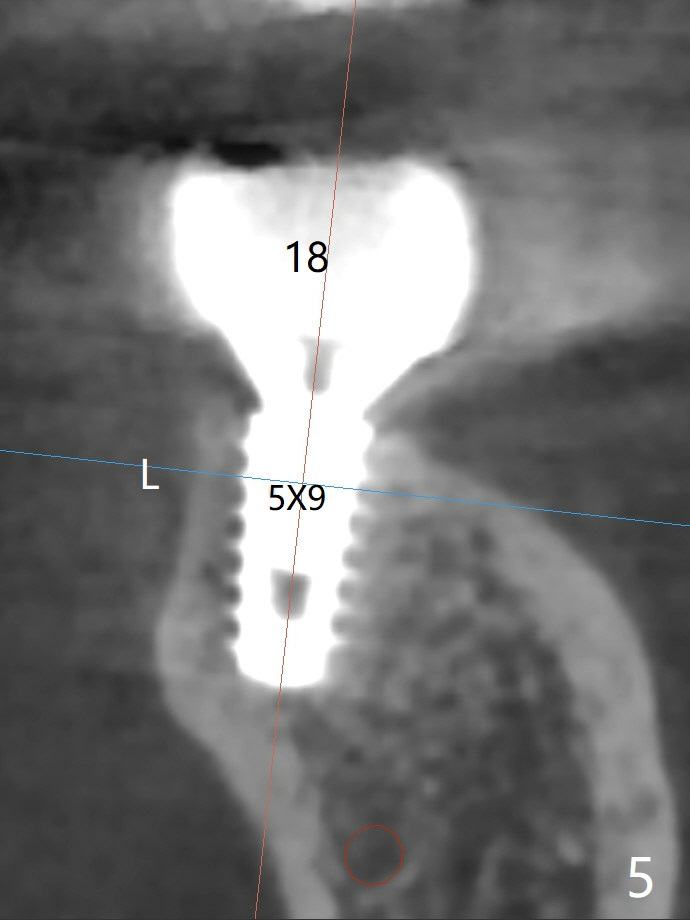

A 71-year-old woman has failed retainer at #31 (Fig.1). Implants will be placed at #31 and 29 for a FPD (Fig.2,3, as compared to Fig.4,5). The ridge at #29 is narrow with thick lingual plate. To avoid buccal deviation, coronal osteotomy overprep will be conducted.